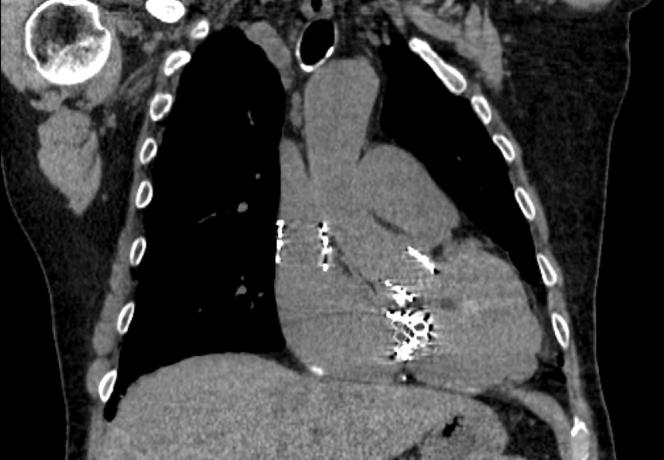

An 84-year-old man with a history of tricuspid valve regurgitation after repair with an incomplete annuloplasty band presented with worsening tricuspid regurgitation. He underwent a transcatheter valve-in-ring procedure, which was complicated by proximal valve embolization. The procedure was salvaged by performing an ad hoc caval implantation, followed by an additional valve implantation within the tricuspid band, with an excellent result.

一名84岁男性,既往因三尖瓣环成形带修复不完全后出现三尖瓣反流,此次因三尖瓣反流加重就诊。他接受了经导管瓣膜置入环内手术,术后出现近端瓣膜栓塞并发症。通过临时腔静脉植入术挽救了该手术,随后在三尖瓣环内额外植入了一个瓣膜,效果极佳。